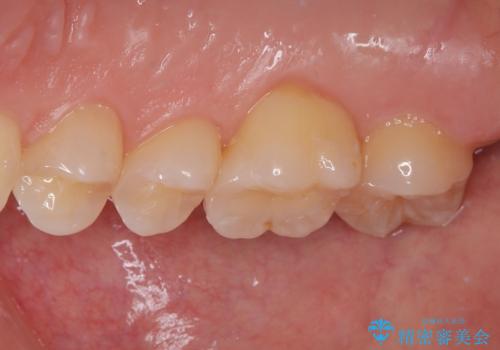

セラミックインレーの装着時には、唾液の侵入を防ぐために、ラバーダム防湿を行いました。

見た目、機能面共に大変喜んでいただきました。

歯と歯の間の虫歯をコンポジットレジンや保険のメタルインレーで治すと段差ができたりして清掃性が悪くなるので、セラミックインレー修復やゴールドインレー修復などの適合の良い詰め物で治療することをオススメします。